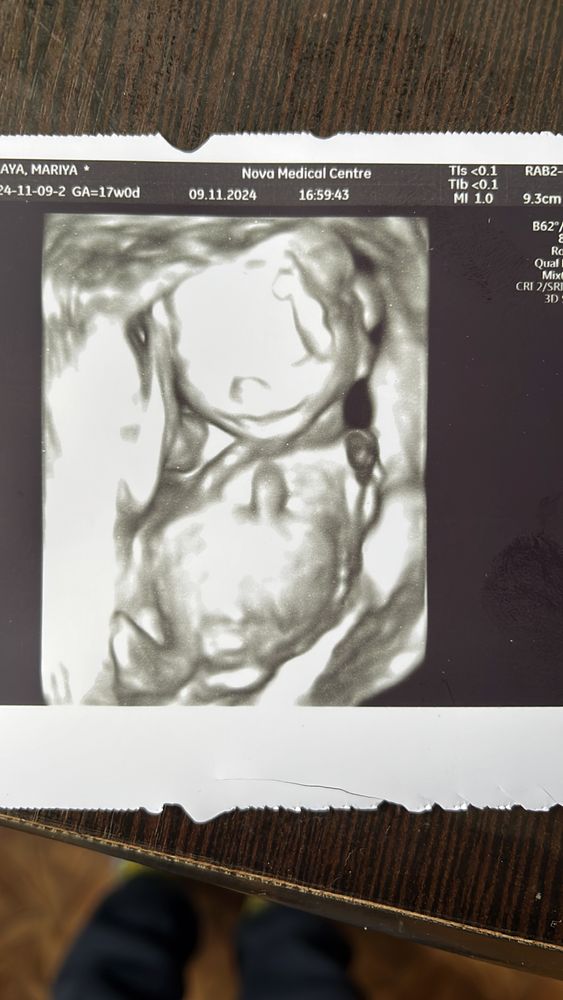

Срок 17-18 недель и у нас очень стеснительная и вредная принцесса👑🥳 все узи пинала датчик,закрывалась ручками и отворачивалась) Единственное что расстроило при осмотре сердечка в левом желудочке лоцируется гиперэхогенный фокус 2,7 мм,будем теперь следить за ним

Здравствуйте, у старшей дочери тоже ставили такой диагноз, 10 лет королевне .Делали УЗИ в годика 2 , сказали всё нормально, не выходит за рамки

Динара Гарифуллина , ну и слава богу) нам сказали что он может к третьему скринингу исчезнуть и ни чего такого криминального